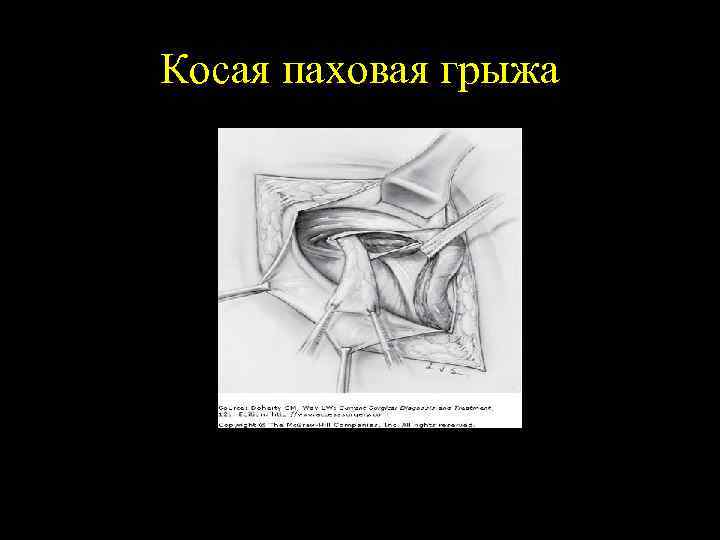

Косая паховая грыжа